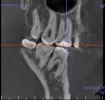

На снимке видно потемнение под пломбой, из-за этого может болеть зуб?

Начал сам более детально снимок рассматривать, показалось, что потемнение под пломбой. Реакции, когда пью холодное или горячее никакой нет.

Ваш снимок должен смотреть специалист в разных ракурсах, так сложно сказать. Вам необходимо обратиться к стороннему специалисту со снимком для консультации.